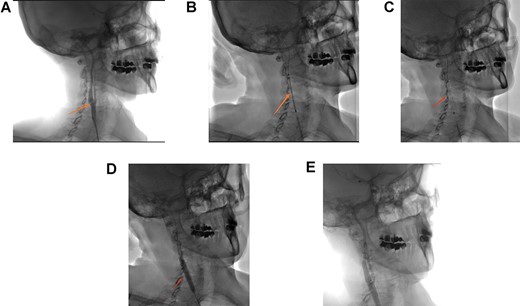

| • Simple follow-up | • Simple follow-up | • Thrombectomy + carotid Thromboendarterectomy by reversal | • Angioplasty + percutaneous stenting (Fig. 5a–e) |

(A) Right carotid angiogram image showing the carotid diaphragm (arrow). (B) Positioning of the carotid stent. (C) Carotid stent release. (D) Stent impaction by angioplasty balloon. (E) Final angiographic control.